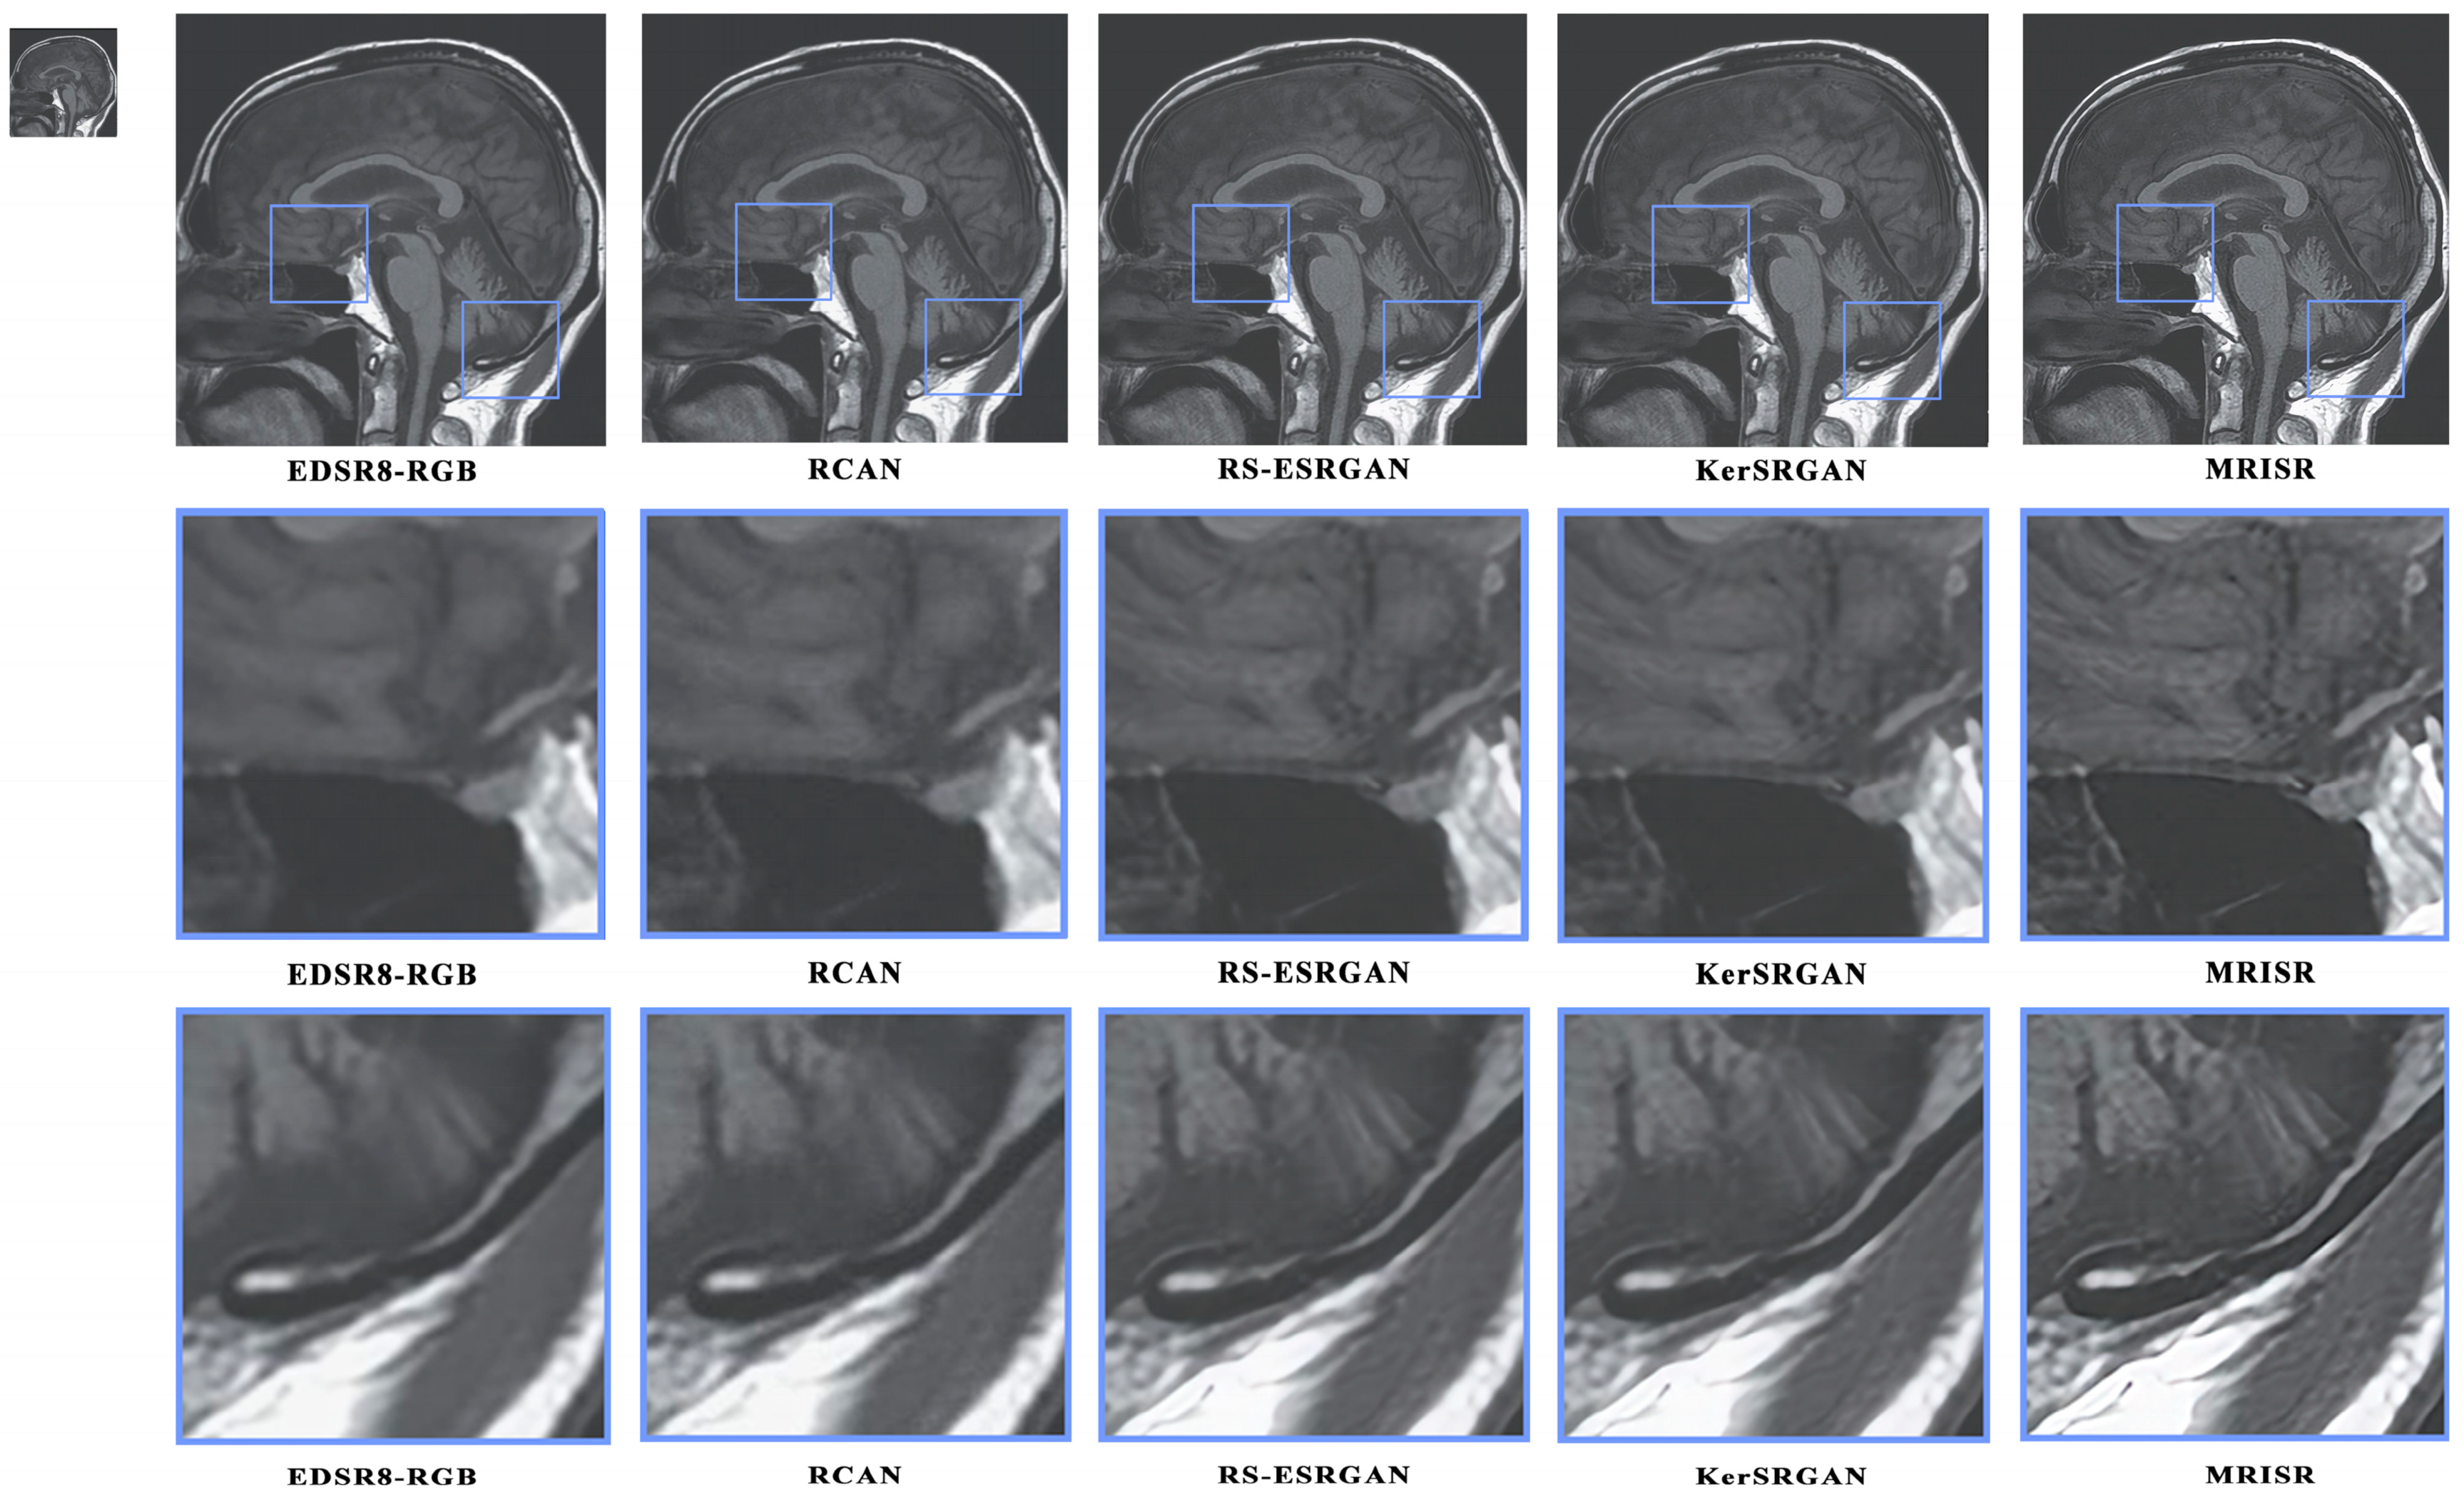

Figure 16 and Figure 17 present a visual comparison of images generated by different algorithms, with the objective of conducting a comprehensive analysis of the performance of various models in the task of image super-resolution reconstruction. Through a detailed examination of images featuring complex terrains, it is evident that, due to the inherent limitations of traditional interpolation algorithms, such as the bicubic method, the processed images exhibit a high degree of blurring and smoothing, ultimately resulting in a significant loss of detailed information. In contrast, while advanced deep learning models, like EDSR8-RGB, RCAN, and RS-ESRGAN, have demonstrated notable advancements in image super-resolution reconstruction, they still exhibit certain deficiencies in accurately distinguishing noise with sharp edges, leading to blurred outputs and unsatisfactory detail recovery. The proposed MRISR model in this paper, however, introduces innovative noise estimation and reconstruction strategies, resulting in generated images that exhibit clearer boundaries between objects and backgrounds, along with more accurate detail recovery. This indicates that our estimated noise distribution is closer to the real noise, thereby effectively enhancing the overall quality of image super-resolution reconstruction. When compared with models such as EDSR8-RGB, RCAN, and RS-ESRGAN, the results of the proposed MRISR model exhibit significantly improved visual clarity, richer details, and no blurring artifacts, fully demonstrating its superiority and effectiveness in the task of image super-resolution reconstruction.

Figure 16. Visual comparison of the generated images.

Figure 17. Visual comparison of the generated images.